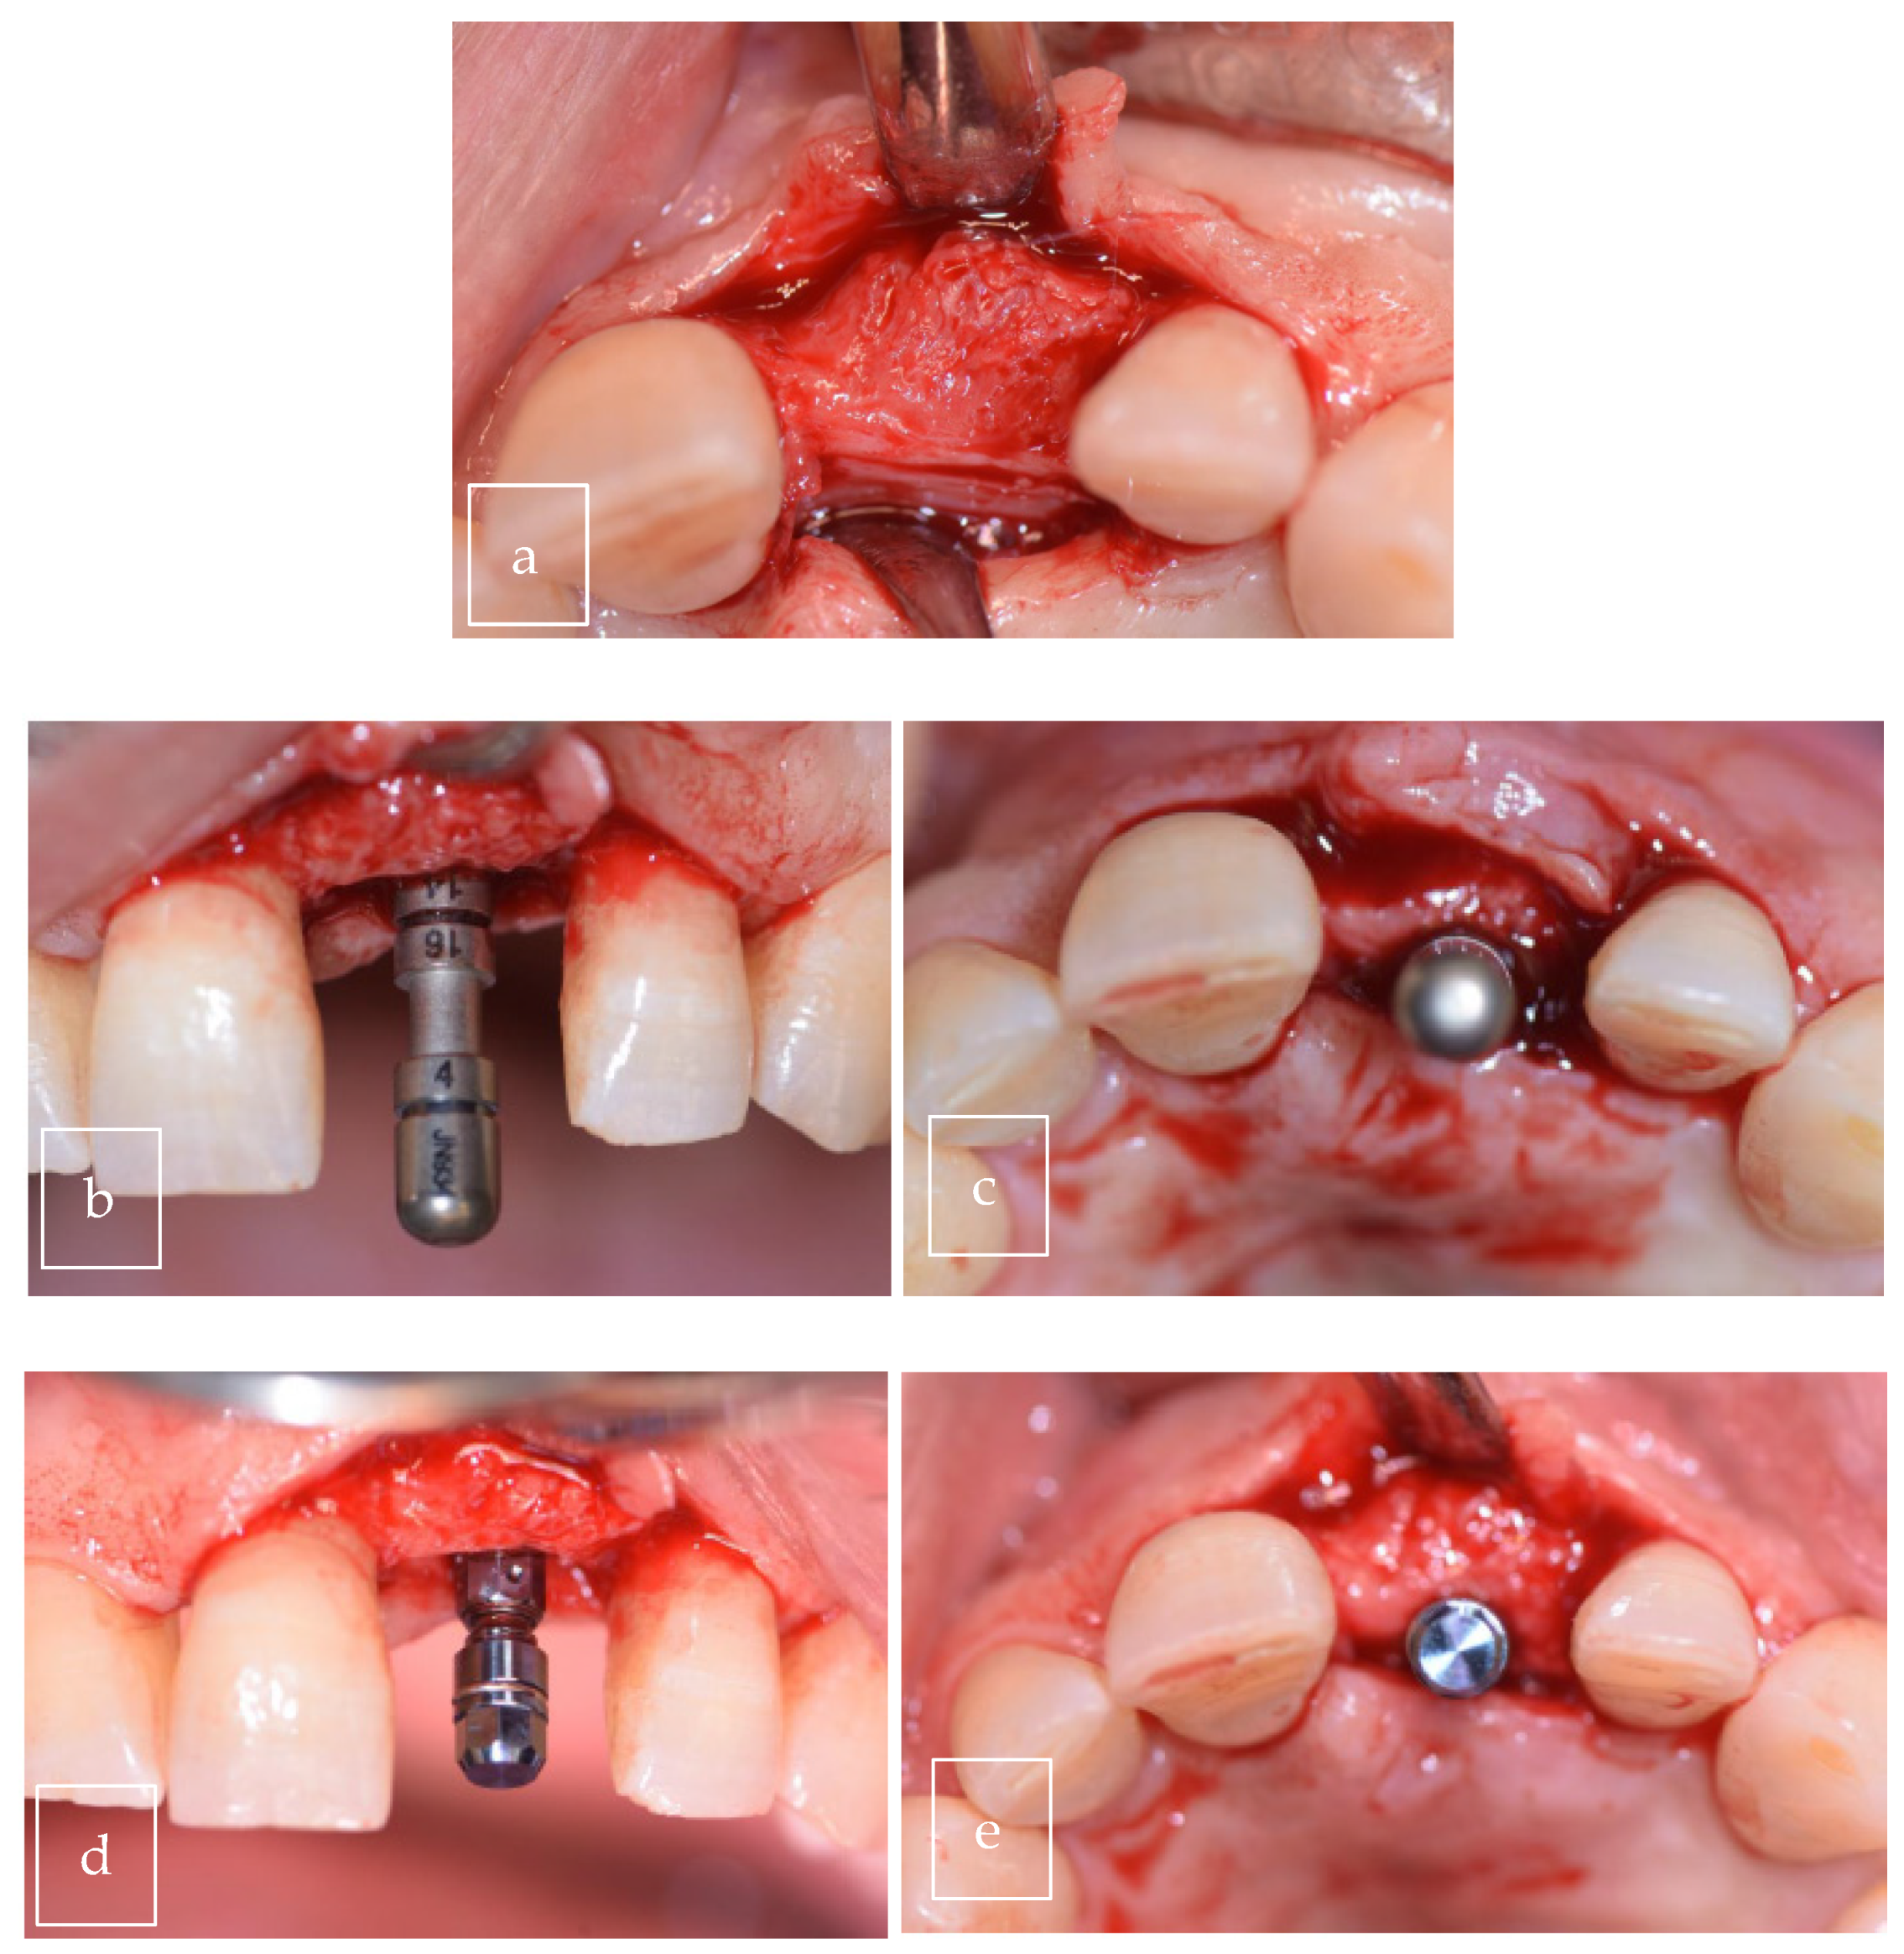

3.2. Case Presentation

| Our case | Case report | 1 | M | 63 | Asymptomatic | Right palate | Surgical excision | 9 × 8 × 12.5 mm | Radiolucent |